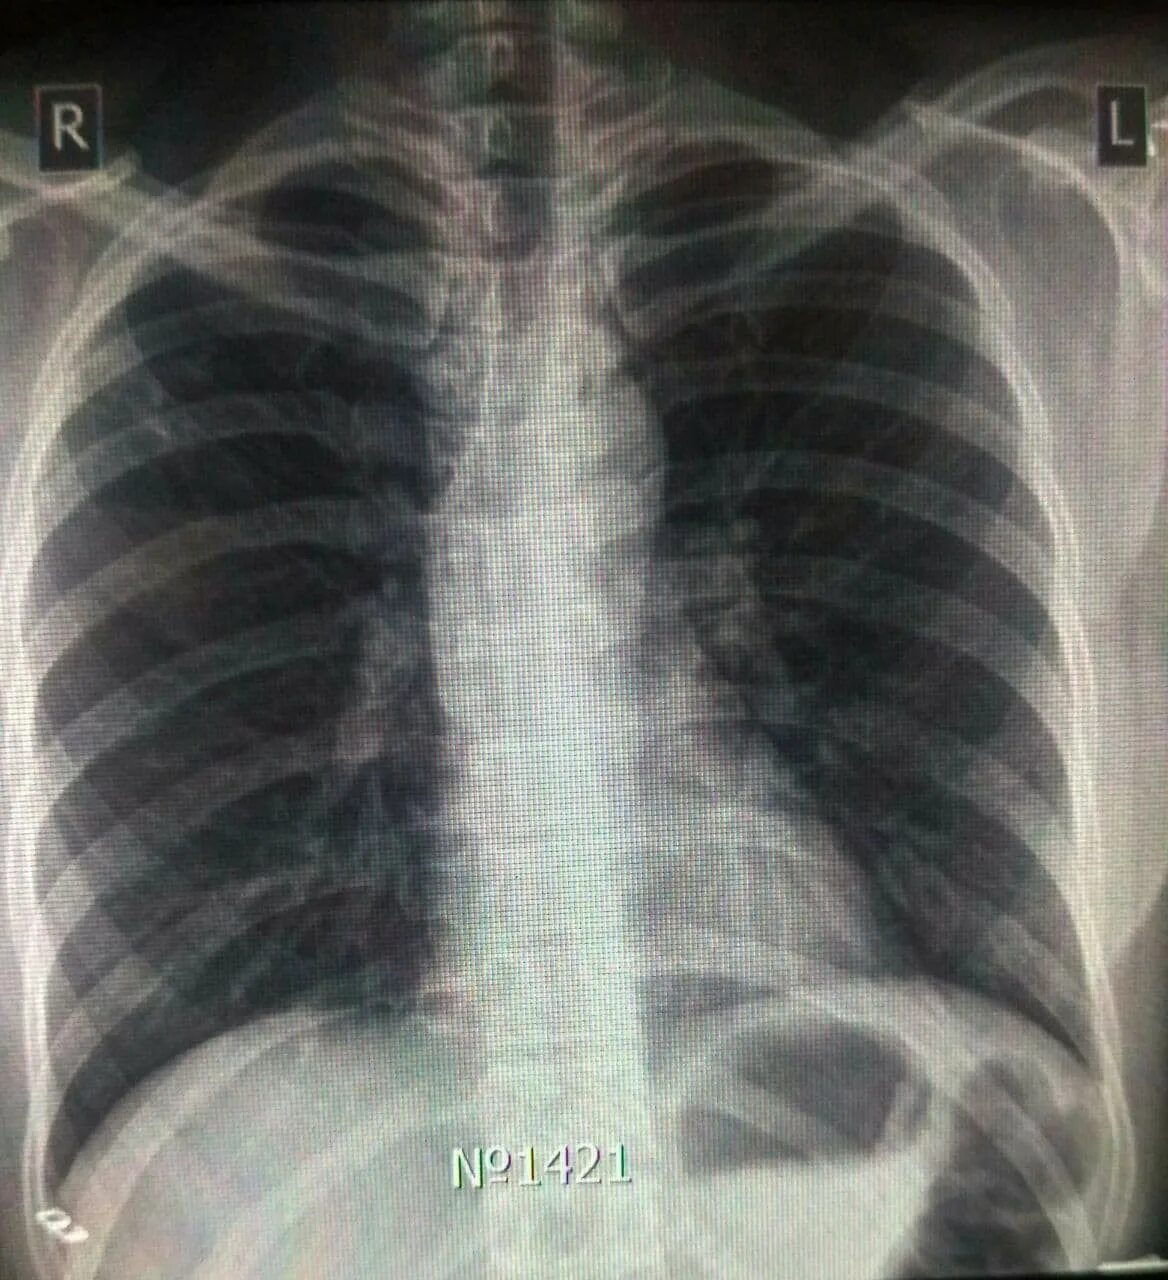

Ренген легких платно